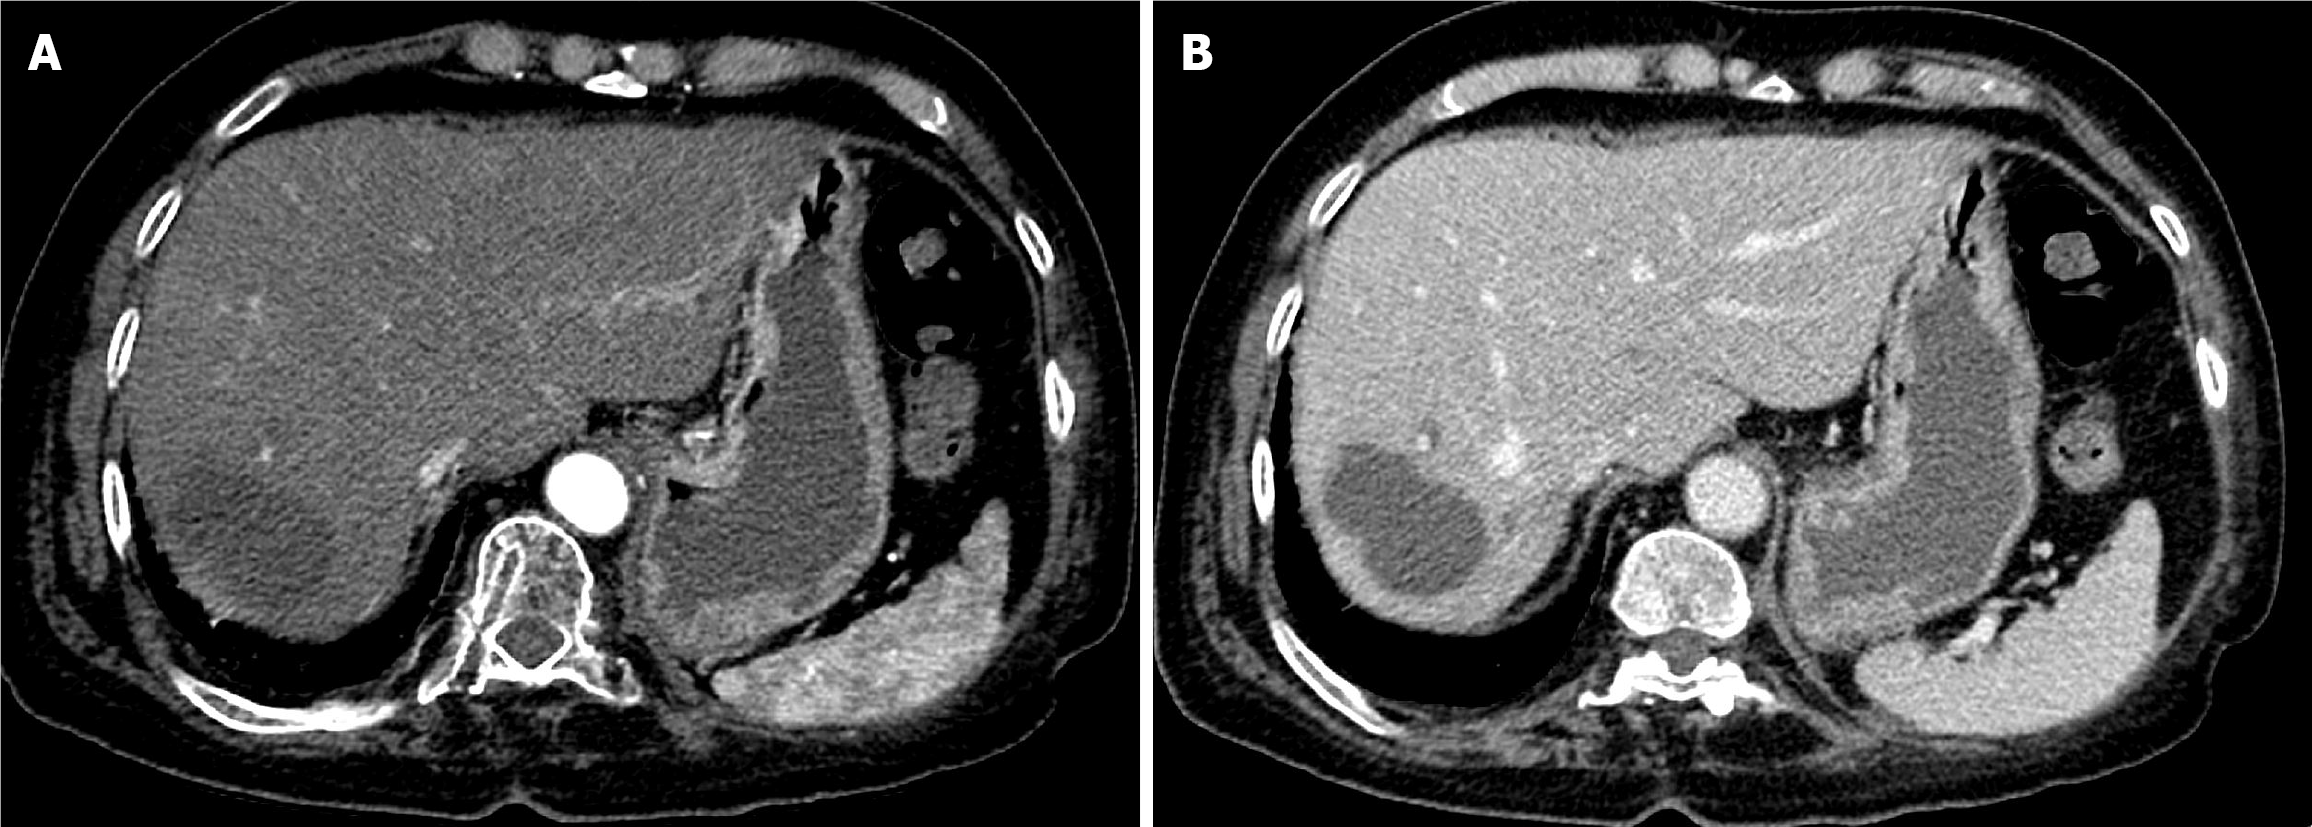

Figure 1 Baseline computed tomography of the abdomen.

A: Arterial phase computed tomography (CT) showed a large, well-defined hypervascular hepatic mass; B: Delayed phase CT demonstrated washout of the mass with an enhancing peripheral rim (tumor capsule).